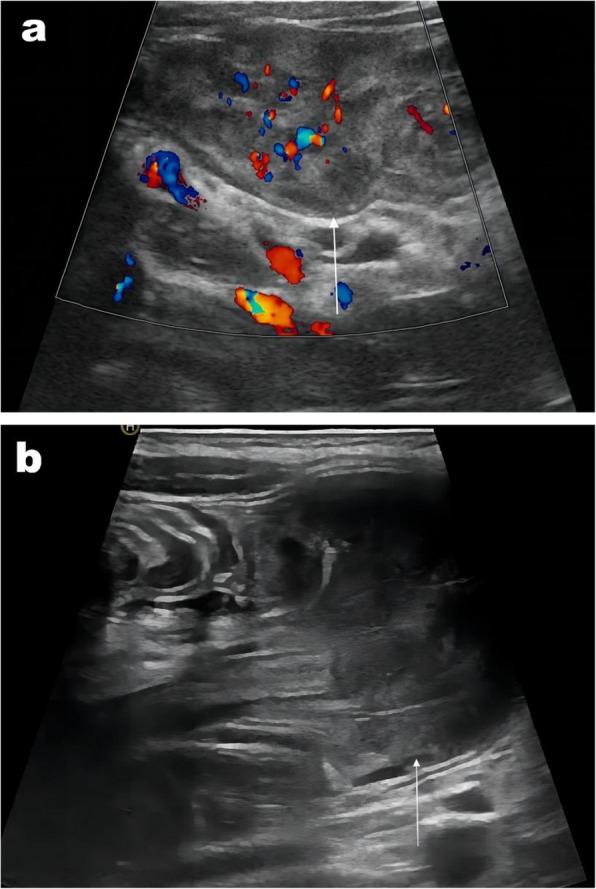

From February 2019 to June 2022, ultrasound (US) features and clinical findings of pediatric patients with small-bowel intussusception (SBI)-including SBI diameter, outer bowel wall thickness, thickness of the head and body of the intussusceptum, length of the intussusceptum, and presence of pathological lead points (PLPs)-were recorded and analyzed. A classification and regression tree algorithm was then used to develop a DTA model, which was trained and validated by randomly categorizing the patients into training (60%, 200/331) and validation (40%, 131/331) datasets to assess diagnostic performance.

A total of 331 patients with SBI (270 with TSBI and 61 with PSBI) were included; the maximum age was 9 years. The initial diagnostic predictor in the DTA model was the detection of a PLP via US, followed by intussusceptum length (P < 0.001). The sensitivity, specificity, and accuracy of the DTA model were 98.2%, 100%, and 98.6%, respectively.